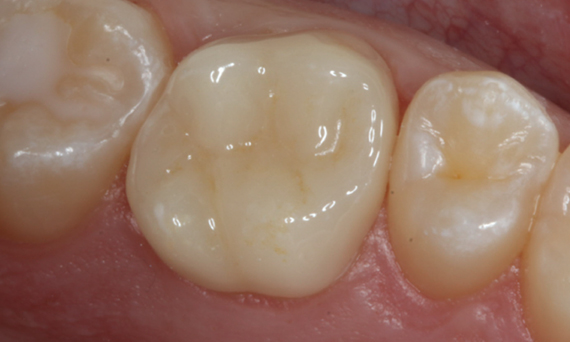

First upper molar in 90 minutes

A CEREC Tessera crown

The restoration of the first upper molar in a single visit was possible due to the efficient CEREC workflow with CEREC Primemill and CEREC SpeedFire. The patient was extremely positive about the short treatment time and the aesthetic result.

Before: First upper molar had been restored with an extensive yet insufficient composite filling that already showed visible fractures.

After: Chairside-fabricated restoration made from an advanced lithium disilicate ceramic, CEREC Tessera.